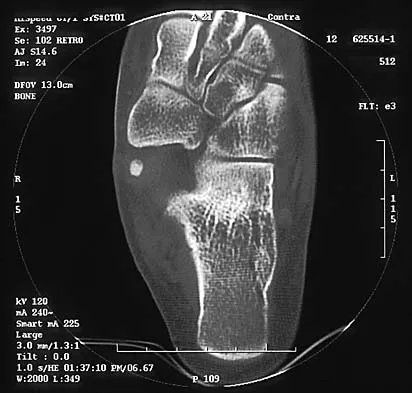

Figures 8a through 8d show the radiographs and CT scans of a 14-year-old girl who has a painful, rigid planovalgus foot. Management consisting of arch supports and anti-inflammatory drugs failed to provide relief. A below-knee walking cast resulted in pain resolution, but she now reports that the pain has recurred. Management should now consist of

Tarsal coalitions commonly present in the preadolescent age group as a rigid, planovalgus foot. Small coalitions of the calcaneonavicular joint or the middle facet of the talocalcaneal joint can be excised with interposition of fat or muscle tissue. Isolated calcaneocuboid joint coalitions are very rare. This patient has an associated large talocalcaneal coalition; therefore, resection is contraindicated. Surgery is warranted after failure of nonsurgical management, and because of the involvement of two joints, the only viable option for the severely symptomatic foot is triple arthrodesis. Vincent KA: Tarsal coalition and painful flatfoot. J Am Acad Orthop Surg 1998;6:274-281.